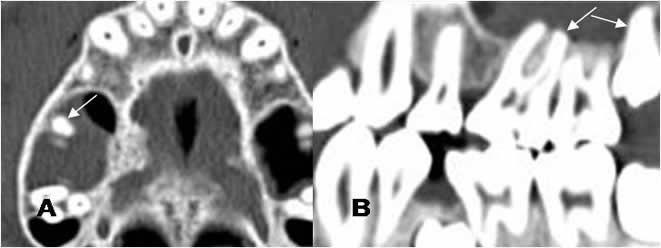

Fig 43. Enfermedad periodontal.

A: TAC axial y B: TAC reconstrucción sagital. Aumento del espacio periapical, por enfermedad periodontal.